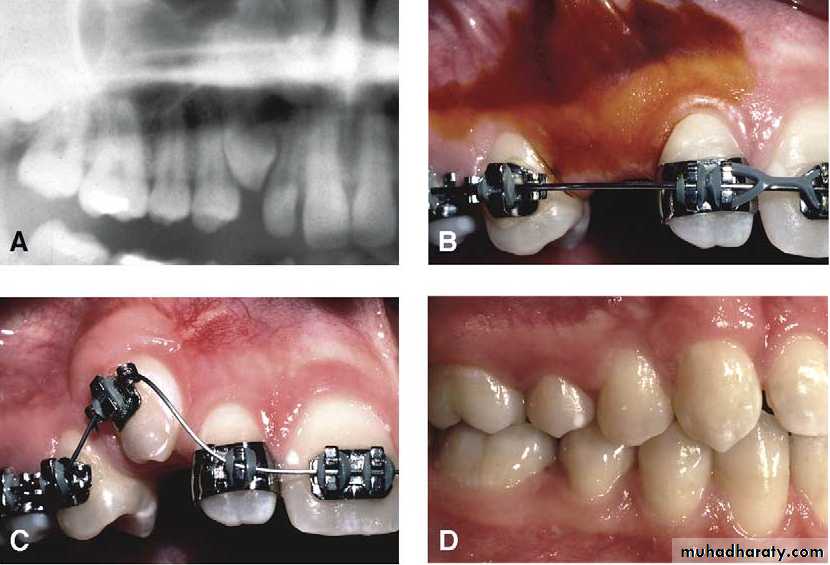

Surgical exposure :the path of eruption is not obstructed

Surgical exposure with orthodontic traction: the path of eruption is obstructed

Surgical exposure with orthodontic treatment (palatal approach )